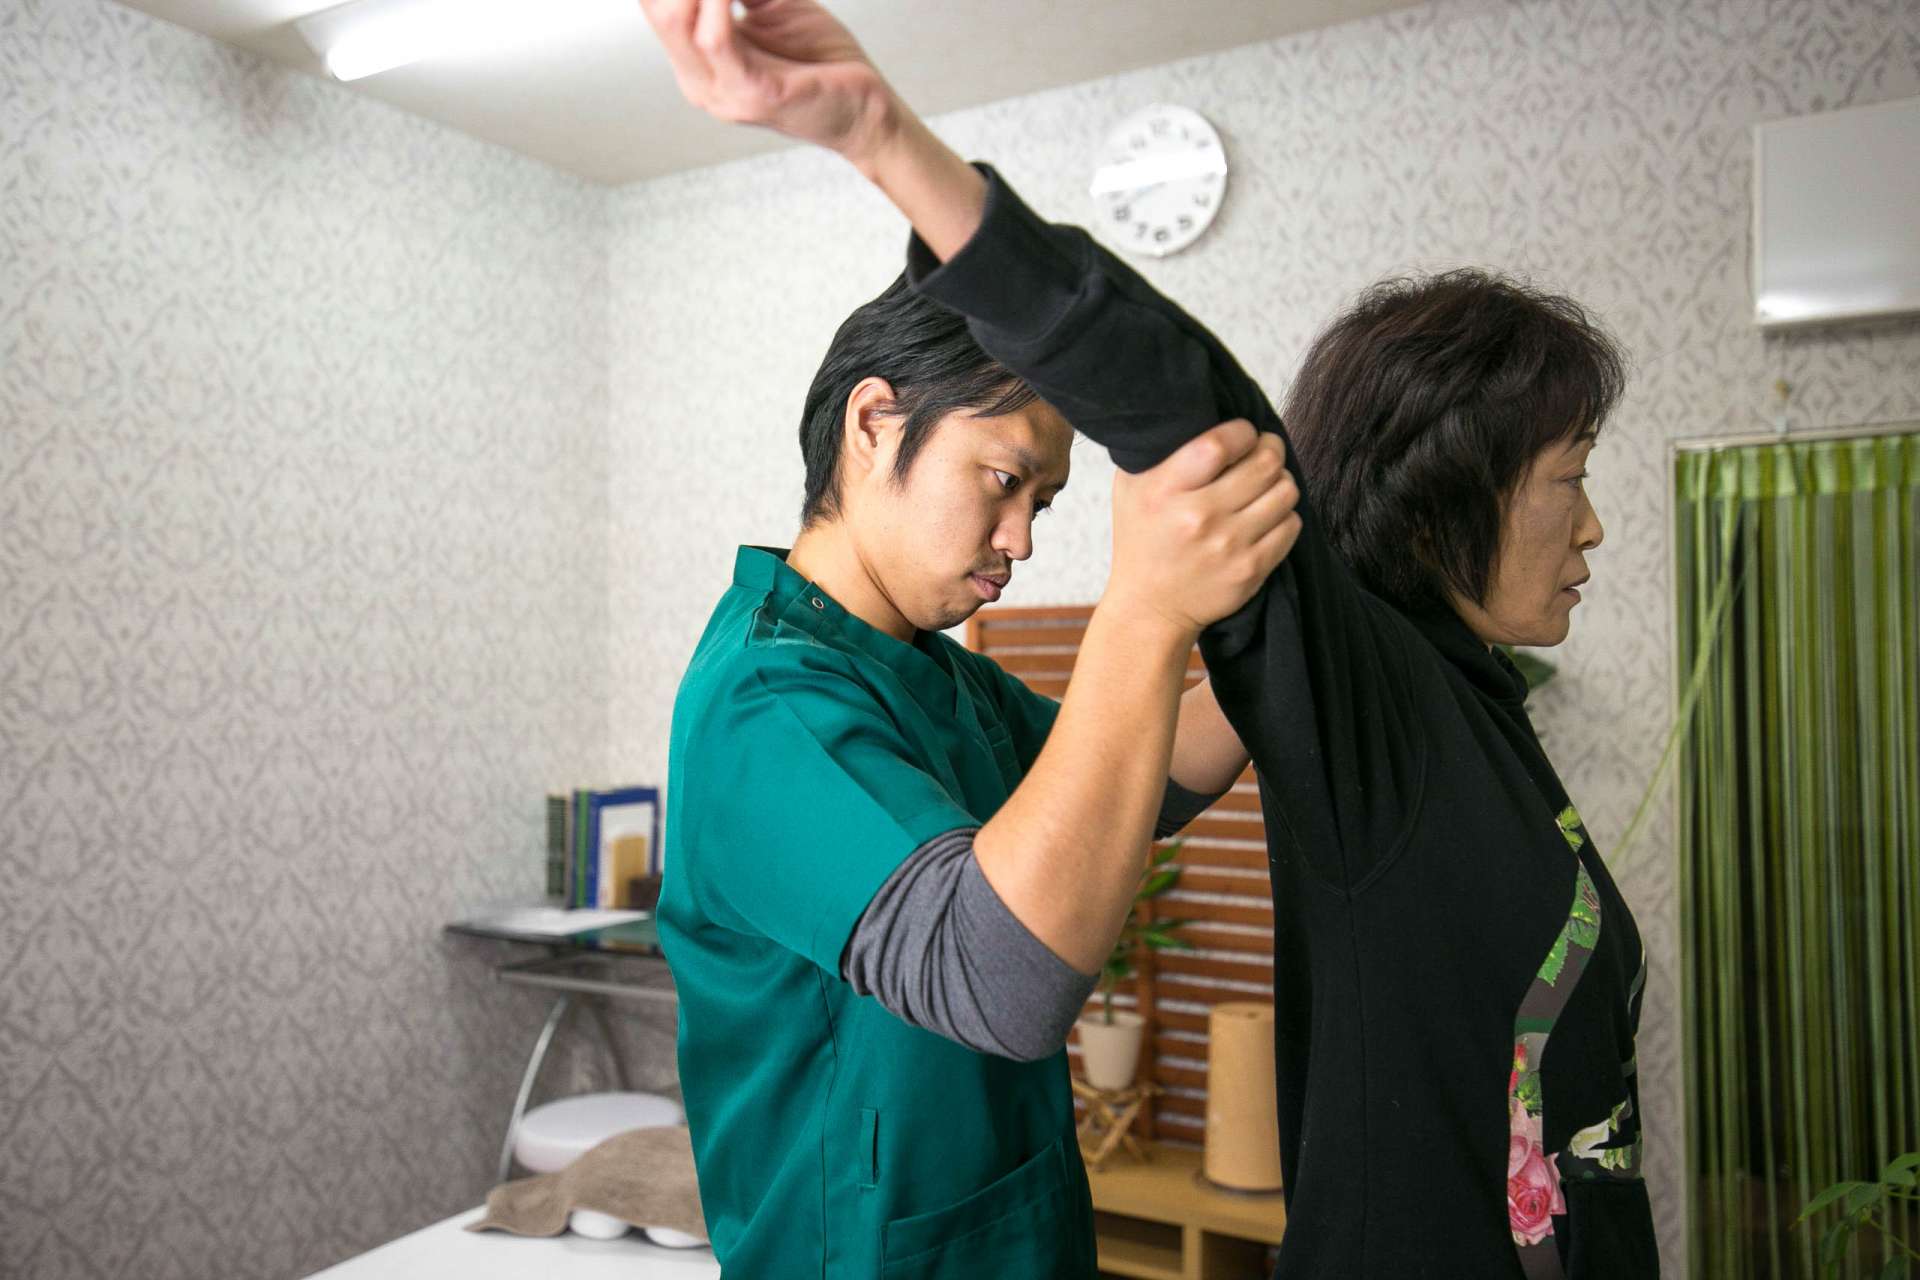

当院では、当院独自の整体法にて「肩が痛い」という症状に対して症状の改善を図ります。

当院へ来られた患者さんをみさせていただくと、胸椎(背骨)全体と右側肋骨の可動性低下と歪み、右肘関節周囲組織の柔軟性低下、右手関節周囲組織の柔軟性低下がみられました。

この患者さんの場合も、以上の背景を踏まえた上で体を調整させていただいたところ、肩を動かしてもほとんど痛みを感じなくなりました。

奈良の橿原にある当院では、こんなふうにして体全体から不具合を特定していき、症状の改善を図っています。